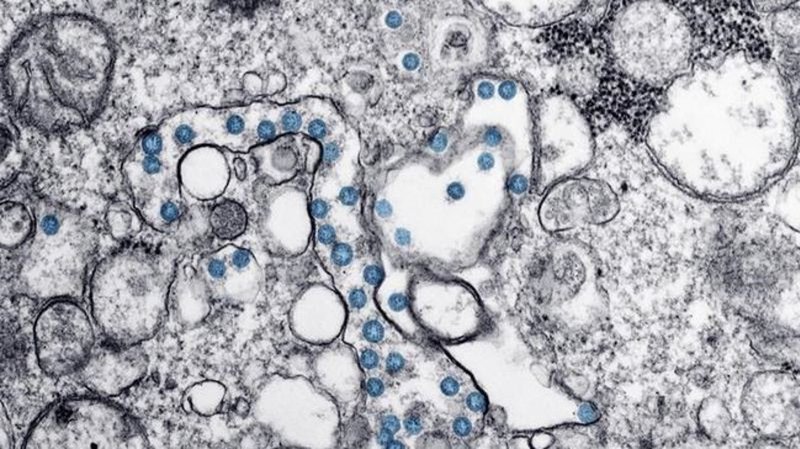

COVID-19 vaccination is expected to ramp up across the country this week as manufacturer Pfizer-BioNTech begins boosting deliveries after a month-long slowdown. The federal government says beginning t...